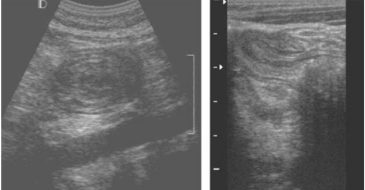

Paciente do sexo feminino, 1 ano e 3 meses, é levada pela mãe ao pronto atendimento pediátrico, com relato de choro forte acompanhado de movimento de flexão das pernas e fezes em “geleia de framboesa”. Com base no quadro clínico e nas imagens ecográficas realizadas no flanco direito, qual é a principal hipótese diagnóstica?